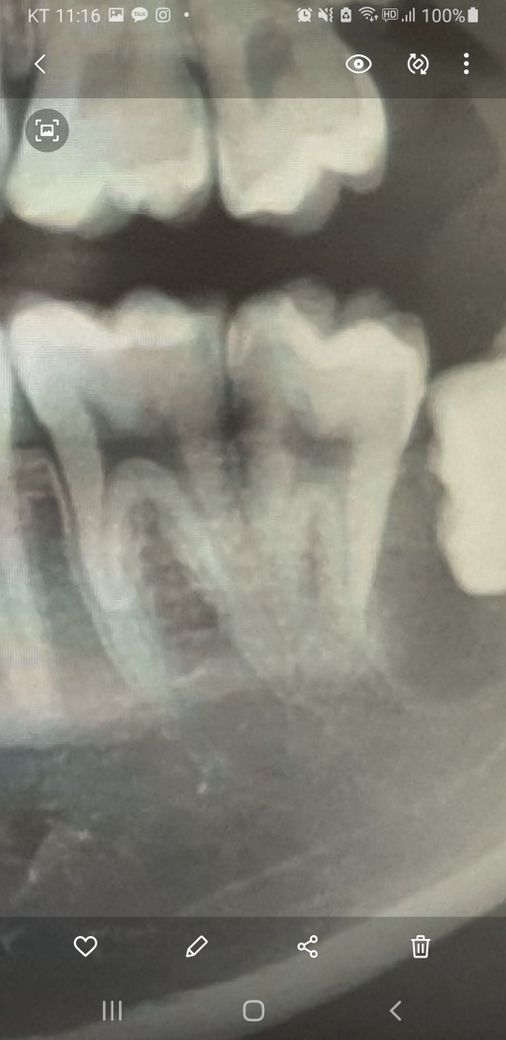

함치성 낭종 때문에 어금니 뿌리 일부분이 흡수되었습니다 파노라마상 흡수가 많이 된 것인지 궁금합니다

뼈가 차오르는 6개월 동안 경과를 지켜봐야 할까요?

• 2번 째 사진

흡수가 상당히 진행이 된 것으로 보입니다. 당장 치료를 하기보다는 지켜보고 결정하면 될 듯 합니다.